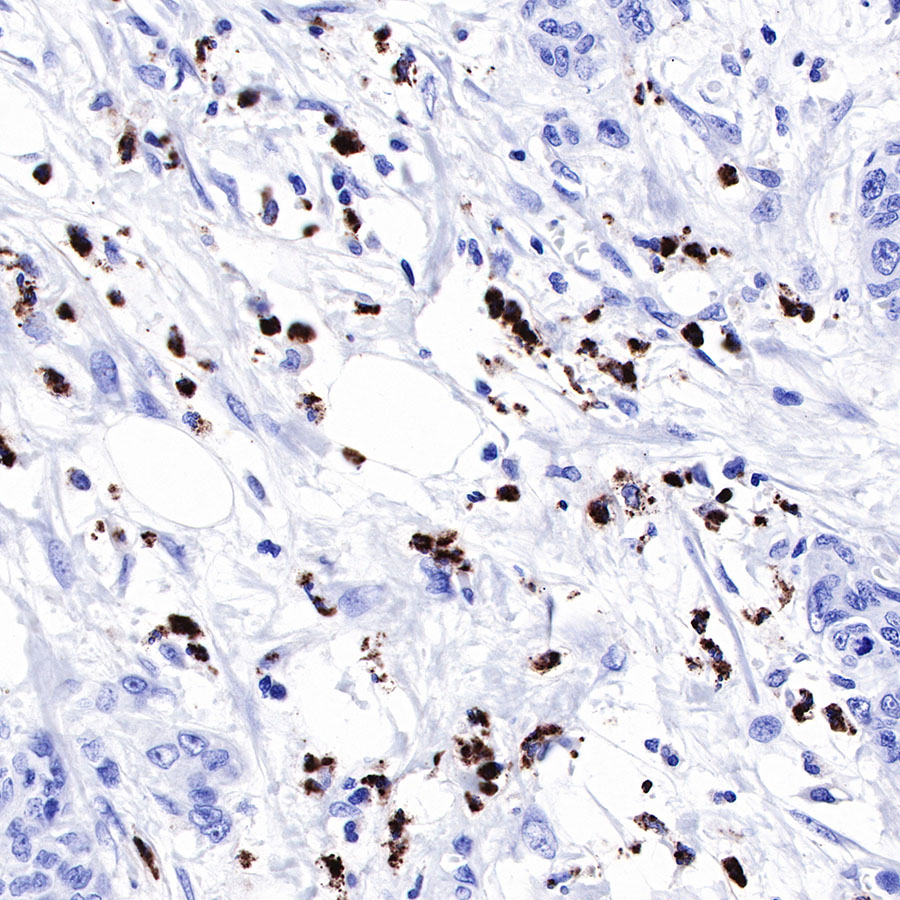

Immunohistochemistry

IHC shows positive staining in paraffin-embedded human lung. Anti-Lysozyme antibody was used at 1/1000 dilution, followed by a HRP Polymer for Mouse & Rabbit IgG (ready to use). Counterstained with hematoxylin. Heat mediated antigen retrieval with Tris/EDTA buffer pH9.0 was performed before commencing with IHC staining protocol.